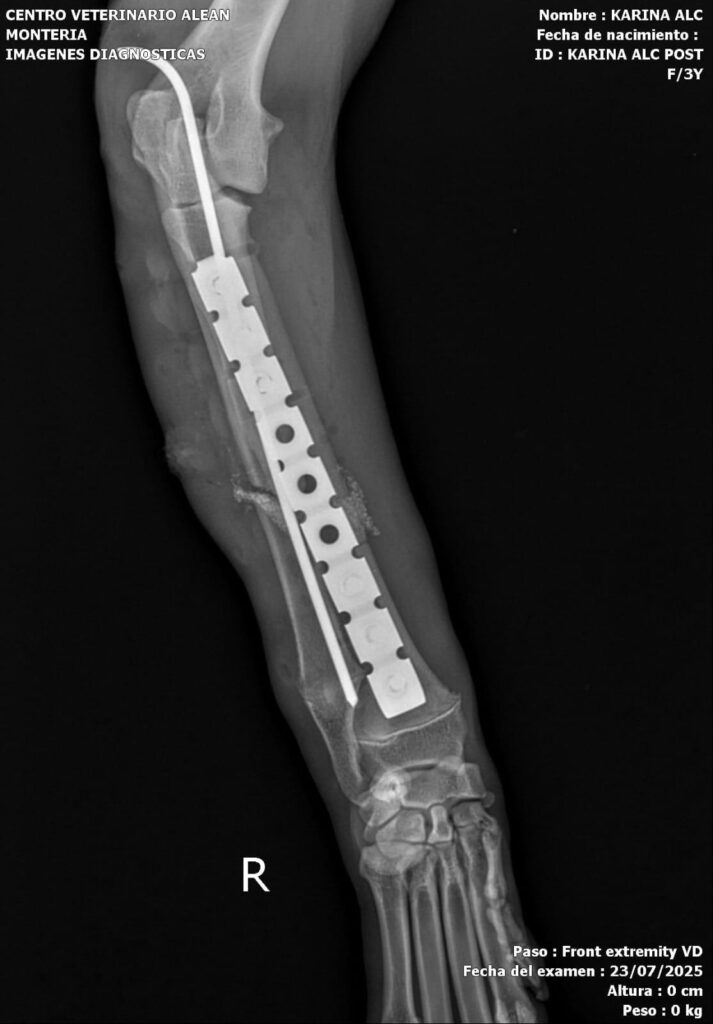

Hoy fue sometida a una tercera cirugía en la mandíbula, en la que se realizó una reconstrucción completa y una reducción total del radio. Además, se le colocó un sustituto óseo a base de silicofosfatos de sodio-calcio en el radio y la ulna.